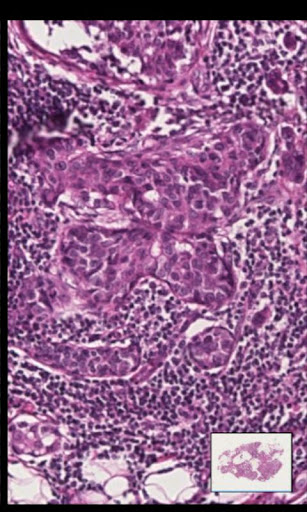

This application allows for a remote pathologist to review and navigate high quality images of diagnostic quality using either the cellular network or WIFI networks on the Android device. Using the application rapid specialist referrals can be made, without access to a computer, a microscope or the original specimen. The pathology image can be reviewed by the pathologist and used to provide a diagnosis used in cancer and other disease treatments.

The user is able to enter the address to their own Aperio Spectrum image server so that the images on their server are then displayed.

Important: This application is intended for use by those who have, or intend to buy a supported image server and requires access to one to work. A example link is provided to the Aperio (CA, USA) image server.